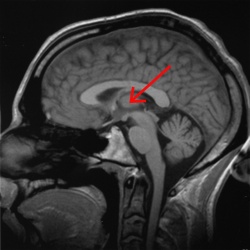

影像學檢查顱內占位性病變,如病變較小,又位於非重要功能區,臨床上可無症狀。若病變位於重要的腦功能區或病變範圍較大,臨床常出現顱壓增高的症狀(如頭痛、噁心、嘔吐等)和局灶性的神經體徵。較大的占位性病變,造成顱壓過高,壓迫腦組織,可造成肢體癱瘓,乃至形成腦疝。腦疝是危及患者生命的徵象,也是顱內占位性病變最嚴重的後果。

顱內占位性病變,常可通過影象學檢查獲得確診。影象學檢查包括頭顱CT掃描、核磁共振檢查及腦血管造影等。現代影象學檢查可顯示占位性病變的位置、大小、形態、數目,還能觀察到病變內部是否有囊變、壞死、鈣化、出血等。腦血管造影是根據血管的部位、形態的改變、循環時間的改變以及病理血管的出現等,間接了解病變的位置、大致形態、含血管是否豐富等。